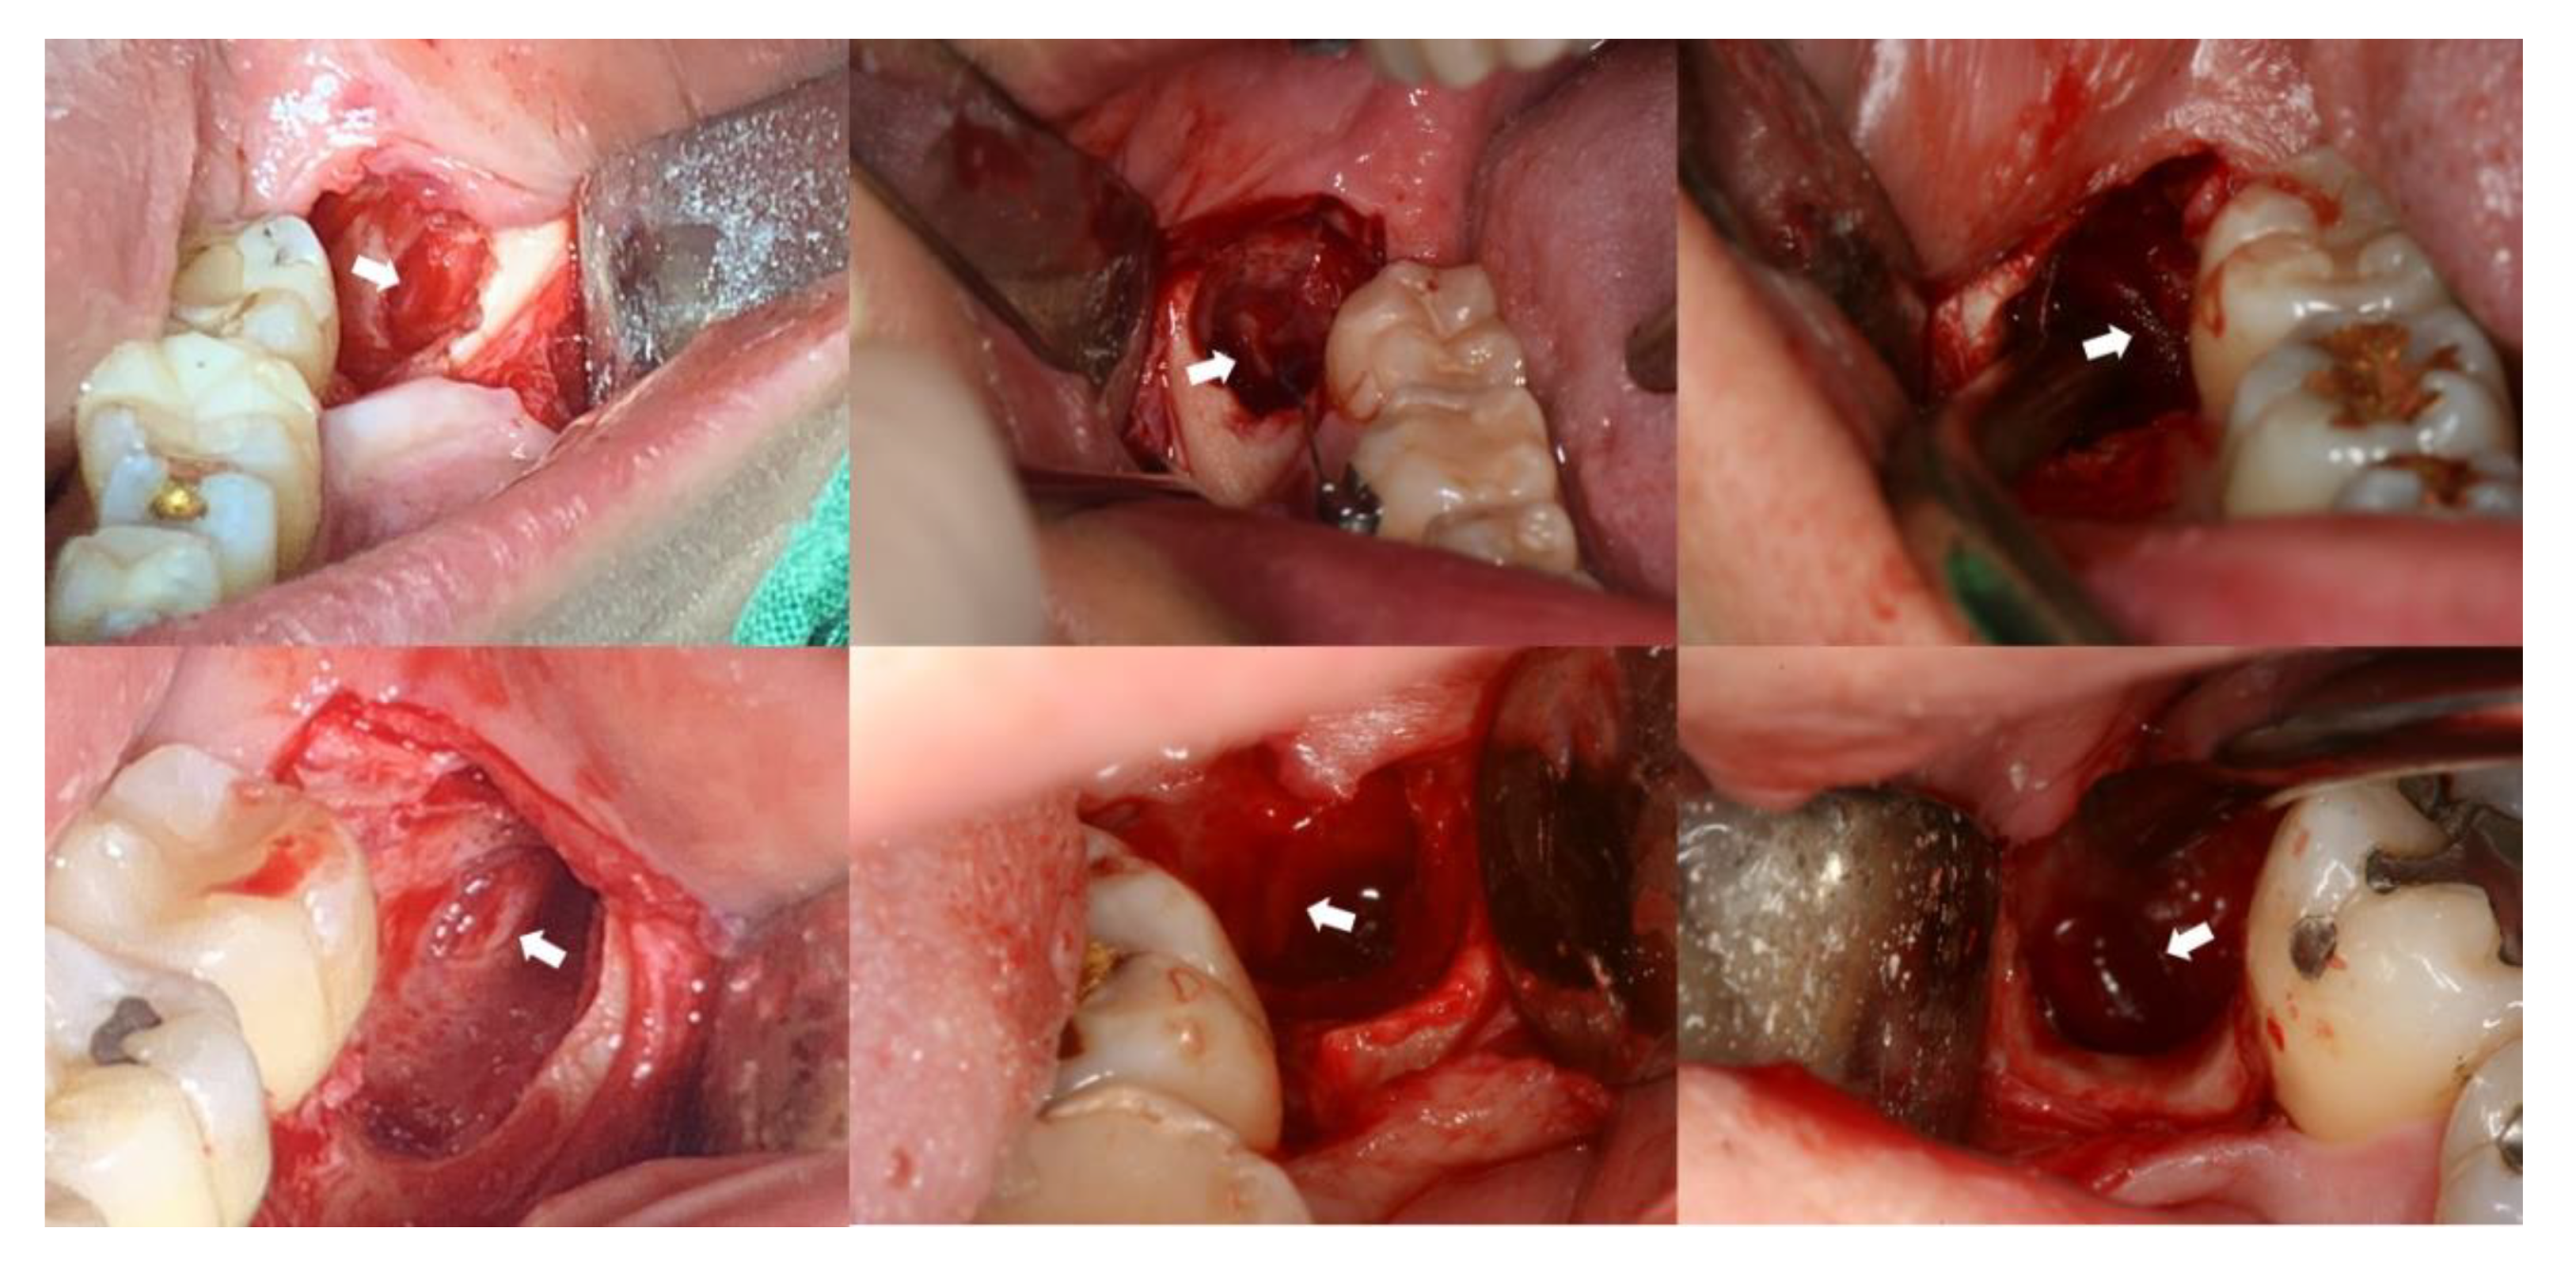

2.3. Surgical Procedure and Identification of IAN Exposure

2.4. Statistical Analysis

3.2. Radiographic Characteristics in the Exposed Group